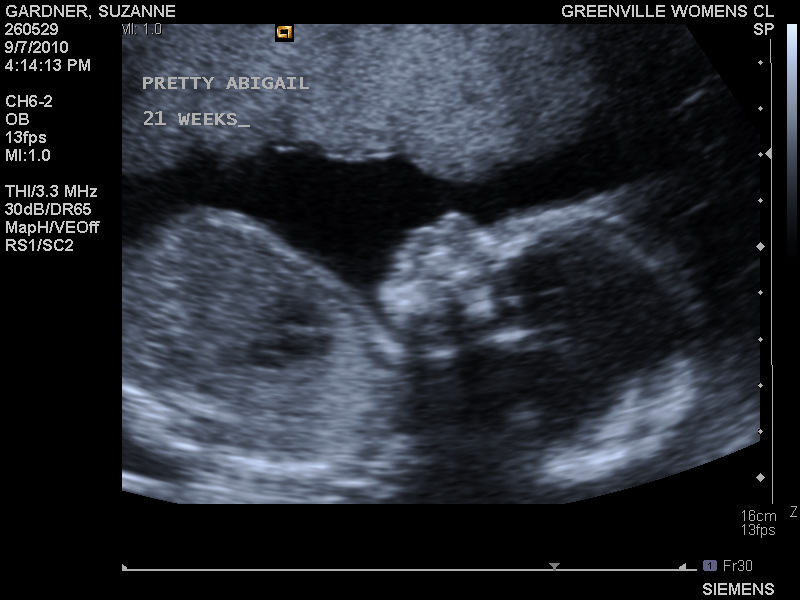

Today, I'm 21w4d and happier than I've ever been. It's taken lots of doctors, lots of tests, lots of medicines, lots of poking and prodding and needles and tears to get here. I've come close to losing my faith more times than I'd like to admit. If it wasn't for my husband, I honestly don't think I would have ever made it. Infertility can make or break a relationship. For us, it made us stronger as individuals, and as a couple.

21w2d

21w2d (foot is 1.5" long)